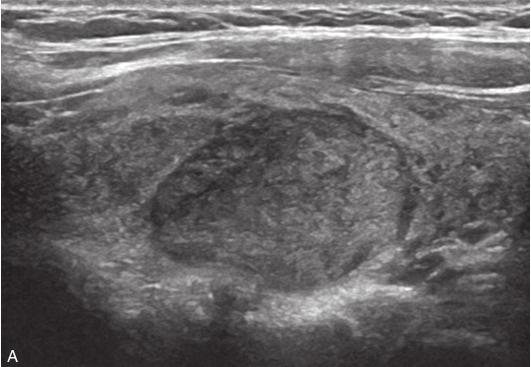

甲状腺右叶中部可见一个肿块,大小约为2.6cm×1.8cm×1.8cm,形状尚规则,边界尚清楚,内部为低回声,分布不均匀,后方回声无变化,CDFI显示肿块内可见丰富的血流信号,见图1-9-1。

图1-9-1 甲状腺髓样癌常规超声图像

A.甲状腺右叶低回声结节纵切面灰阶超声图像;B.甲状腺右叶低回声结节横切面灰阶超声图像;C.CDFI图像